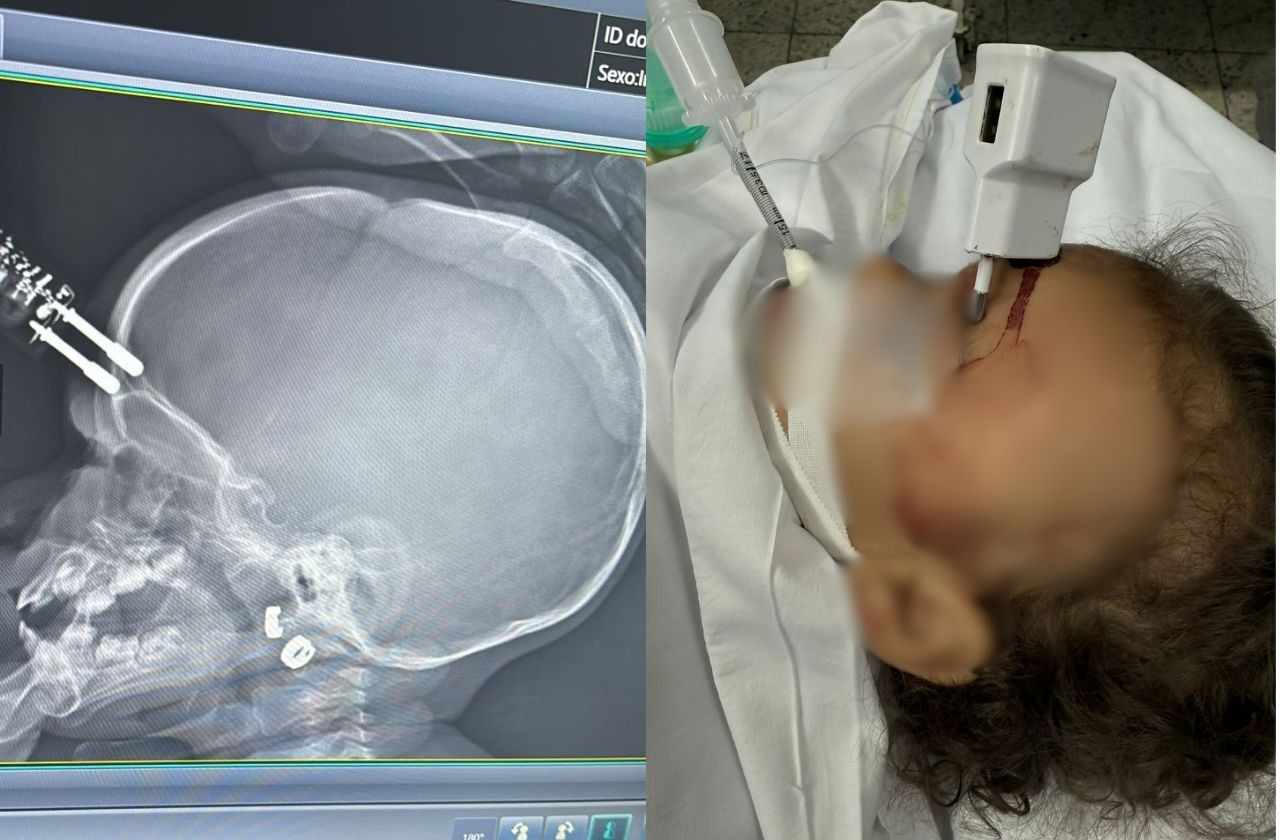

Uma menina de 1 ano e quatro meses sofreu um grave acidente doméstico em Divinópolis, na região oeste de Minas Gerais, ao cair da cama e atingir a testa em um carregador de celular que estava no chão.

O objeto ficou cravado na cabeça da criança, que precisou ser submetida a cirurgia de emergência.

Ela acionou o Samu, que realizou o atendimento e encaminhou as duas para a UPA. Segundo o neurologista Bruno Castro, que atendeu o caso, o carregador chegou a perfurar o crânio da menina, provocando uma fratura.

Ela foi inicialmente atendida na Unidade de Pronto Atendimento (UPA) de Divinópolis e, em seguida, transferida para o Hospital São João de Deus, onde passou por cirurgia imediata para retirada do objeto, correção da lesão e contenção de um pequeno sangramento.